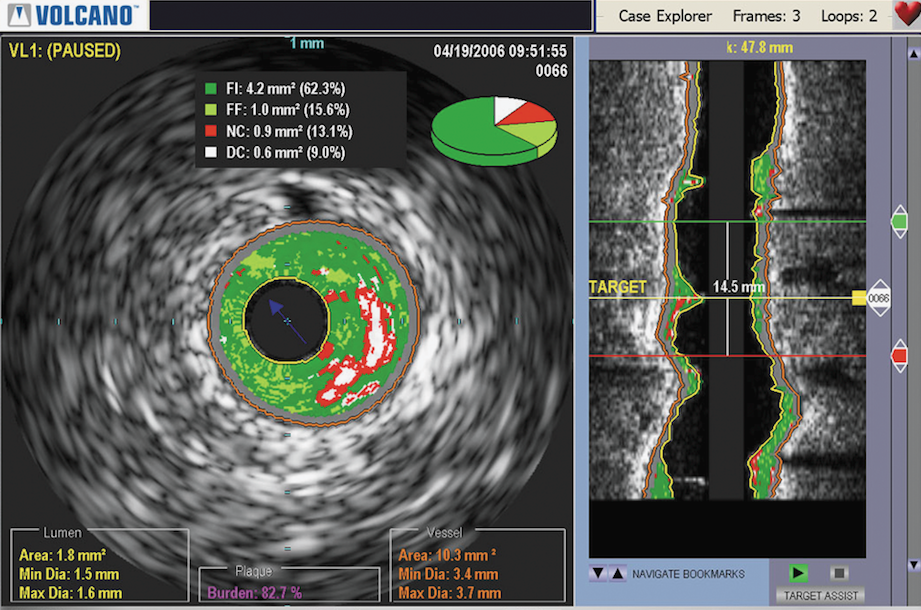

The purchase will enable Philips to further expand its advanced imaging capabilities of its angiography suite. Volcano is a leader in intravascular ultrasound (IVUS) and fractional flow reserve (FFR) catheter measurements used in the interventional cardiology cath lab. The additional technology will enhance Philips' angiography imaging system suite offerings.

With 2013 sales of approximately $400 million, San Diego, California-based Volcano is a leader in catheter–based imaging and measurements for minimally invasive diagnostics and treatment of coronary artery disease and peripheral vascular disease. Volcano is the only company in the industry with a leading position in both IVUS imaging and FFR measurements. In addition, the company possesses the broadest product portfolio around these two technologies, a leading IP position and a nascent peripheral vascular therapeutics business that targets a segment with a double-digit growth rate.